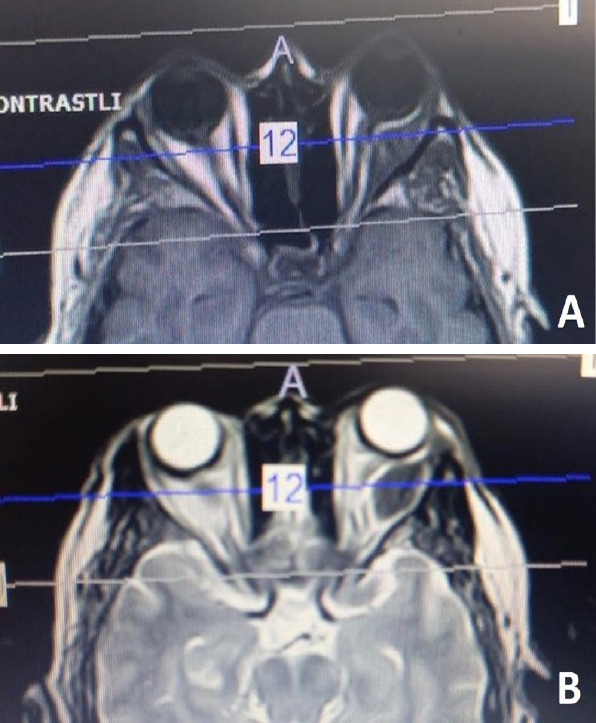

转移性疾病是眼眶肿瘤的一个相对罕见的病因。虽然有许多不同类型的原发性恶性肿瘤被记录在案,但其中以肺癌和乳腺癌最为常见。本文报告了三例乳腺癌眼眶转移病例。第一例患者无原发性恶性肿瘤病史,最初表现为晚期乳腺癌眼眶转移。第二例患者曾接受新辅助化疗、乳房切除术和辅助放疗。经诊断,该病的复发是通过有症状的眼眶转移累及外侧直肌。第三例患者曾接受乳房切除术、辅助放疗和激素治疗。考虑到即使没有诊断出原发性恶性肿瘤的患者也可能出现眼眶转移,眼科医生对此问题的认识至关重要。

Metastatic disease is a relatively rare cause of orbital tumors. While many different types of primary malignancies have been documented, lung and breast cancers are the most prevalent ones among them. Herein, three cases of orbital metastasis from breast cancer are reported. The first patient had no history of primary malignancy, and the initial presentation was orbital metastasis from advanced breast cancer. The second patient had a history of neo-adjuvant chemotherapy, mastectomy, and adjuvant radiotherapy. The recurrence of the disease was diagnosed via symptomatic metastasis to orbit involving the lateral rectus muscle. The third patient had a history of mastectomy, adjuvant radiotherapy, and hormone therapy. Considering that even patients without a diagnosis of primary malignancy may present with orbital metastasis, ophthalmologists' awareness of this issue is critical.